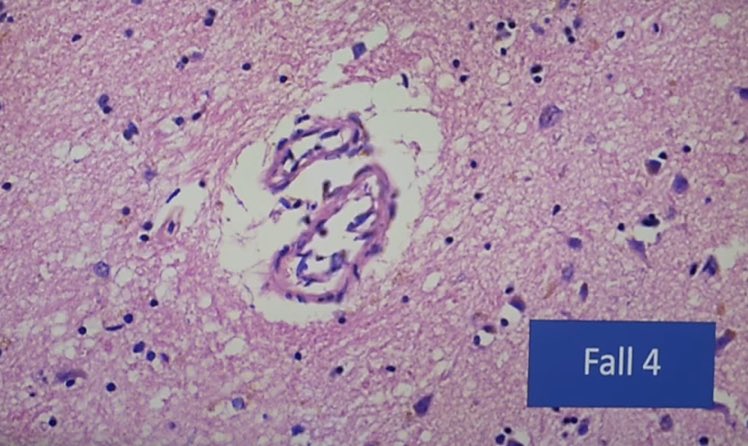

الأعراض الجانبية المشتبه بها:

الآثار الجانبية المشتبه بها للقاح كورونا ذات العواقب المميتة المحتملة:

- ظواهر المناعة الذاتية ("الهجوم الذاتي")

-تلف الأوعية الدموية "التهاب البطانة" ، التهاب الأوعية الدموية ،